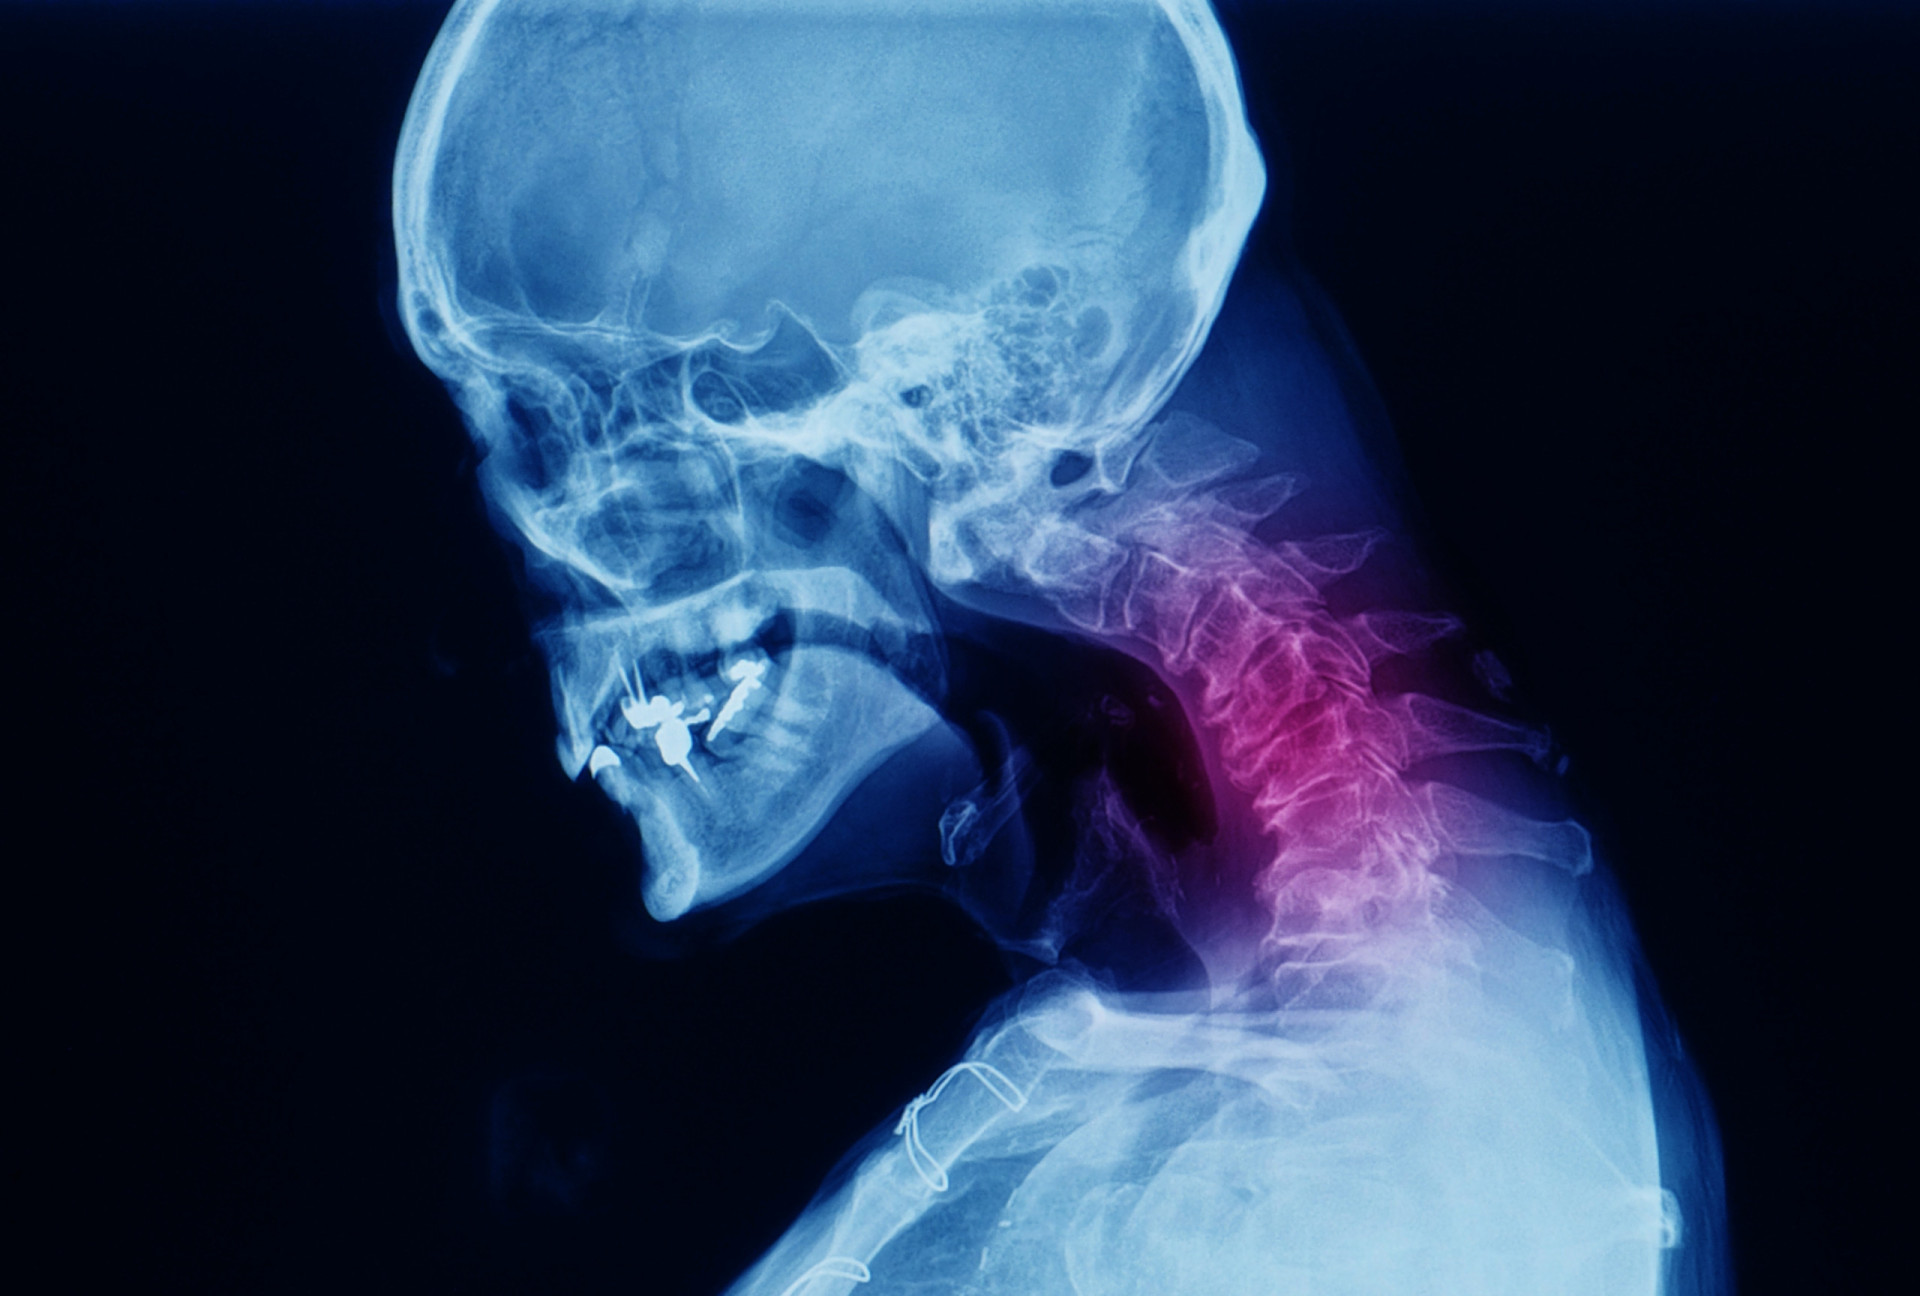

Arthritis in the neck, also known as cervical arthritis, is a common condition that affects the joints in the neck. This degenerative condition can cause significant discomfort and limit mobility, impacting daily activities and quality of life. Understanding the causes, symptoms, and treatment options for arthritis in the neck is crucial for managing this condition effectively.

Arthritis in the neck occurs when the cartilage between the vertebrae in the cervical spine wears down, leading to inflammation and pain. This condition is often associated with aging but can also result from injuries, infections, or genetic factors. The most common types of arthritis affecting the neck are osteoarthritis and rheumatoid arthritis.

• Imaging Tests: X-rays, MRI, or CT scans to visualize the bones and soft tissues in the neck.